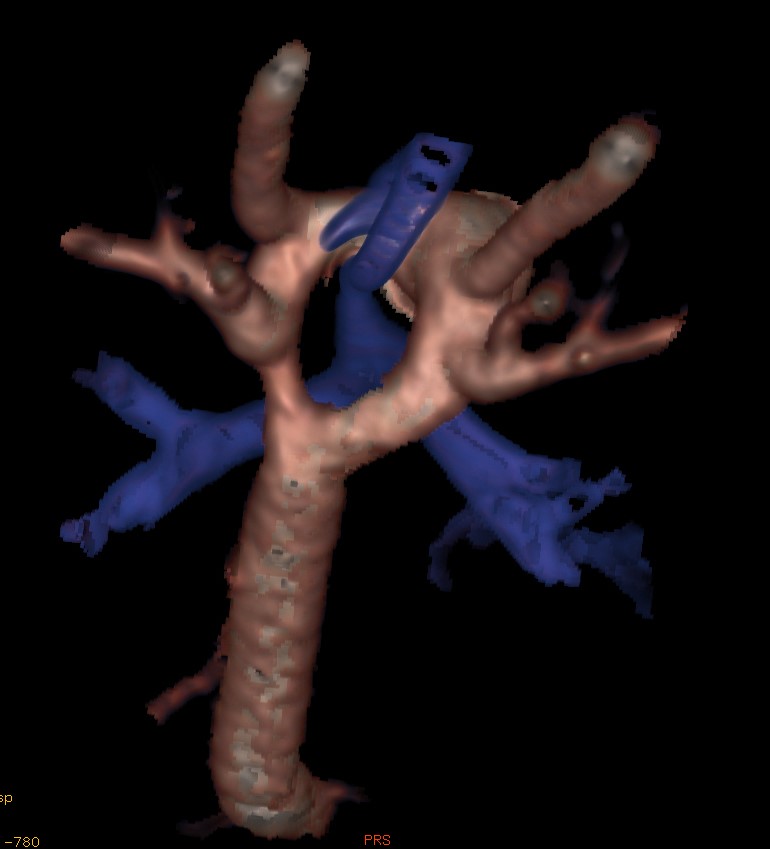

Catheter thermoablation can be performed to prevent atrial fibrillation. For the planning and the implementation of this procedure it is necessary to know the precise anatomic arrangement of the left ventricle and the pulmonary vein ostium. Both, MRA and CTA examinations can provide the necessary 3D information for these procedures.

8.1.7. Diseases of the Pericardium